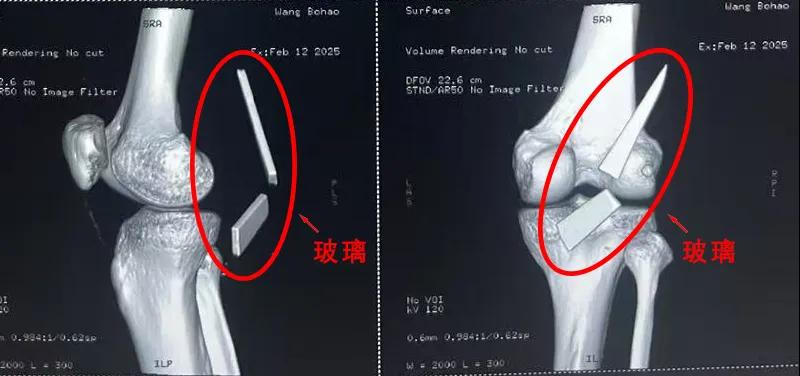

患者家屬這才開始意識到問題的嚴重性,便帶著孩子到鄉(xiāng)鎮(zhèn)衛(wèi)生院檢查——結(jié)果顯示右膝關(guān)節(jié)后方竟然殘留著兩塊兒鋒利的碎玻璃,測量后預(yù)估玻璃總長將近13厘米!

由于玻璃位置毗鄰坐骨神經(jīng)和股動脈,一旦刺破股動脈,將嚴重威脅生命。家屬著急萬分,想著能否盡快手術(shù)取出碎片,于是慕名來到漯河醫(yī)專二附院(漯河市骨科醫(yī)院、漯河市立醫(yī)院)手顯微外科(修復(fù)重建骨感染科)。

術(shù)中,馬廣輝醫(yī)生憑借扎實的理論知識和嫻熟的顯微外科技術(shù),順利找到深深刺進肌肉的兩塊玻璃,肉眼可見玻璃尖端距股動脈僅有不到半公分的距離!如果患者再耽誤半天或者再多活動幾次膝關(guān)節(jié),小指粗的股動脈很有可能被玻璃扎破,后果難以想象。

最終,馬廣輝醫(yī)生在血管、神經(jīng)表面順利取出兩塊玻璃碎片,拆除了埋在患者膝關(guān)節(jié)的“炸彈”。在告知患者家屬術(shù)中情況后,家屬懸著的心終于放了下來。